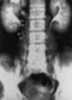

Duplication with ectopic ureterocele

A ureterocele is a congenital abnormality found in the ureter. In this condition the distal ureter balloons at its opening into the bladder, forming a sac-like pouch. [Source: Wikipedia ]